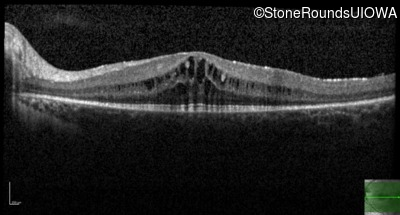

Optical Coherence Tomography - Right - 20/32 -1

Exemplar / OCT Stack

OCT Stack